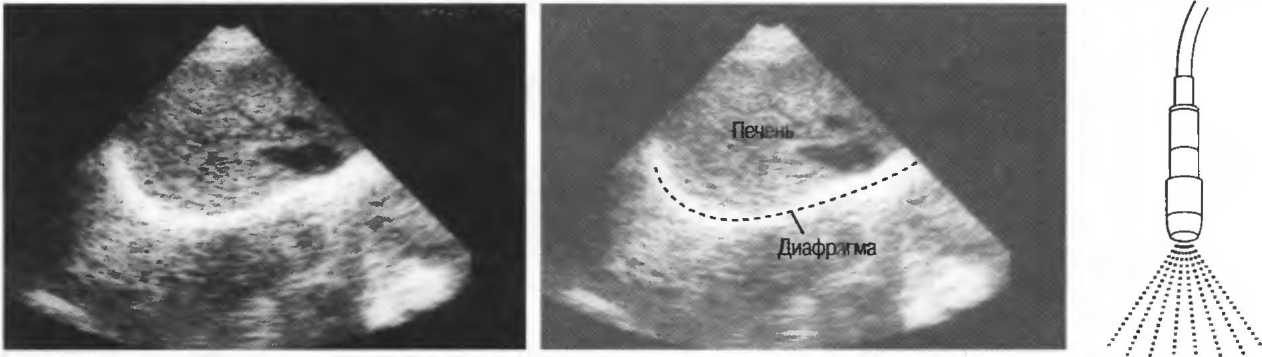

Череп плода, дифрагма, стенки сосудов, соединительная ткань являются примерами зеркальных отражателей (рис. 6).

Рис.6. Сагиттальный срез печени: имеется очень сильное (зеркальное) отражение от диафрагмы, являющейся таким мощным отражателем, что изображение печени повторяется за ней. Ультразвуковые волны проходят через печень после излучения, затем повторно — после отражения от диафрагмы, затем — от поверхностей тканевых структур.